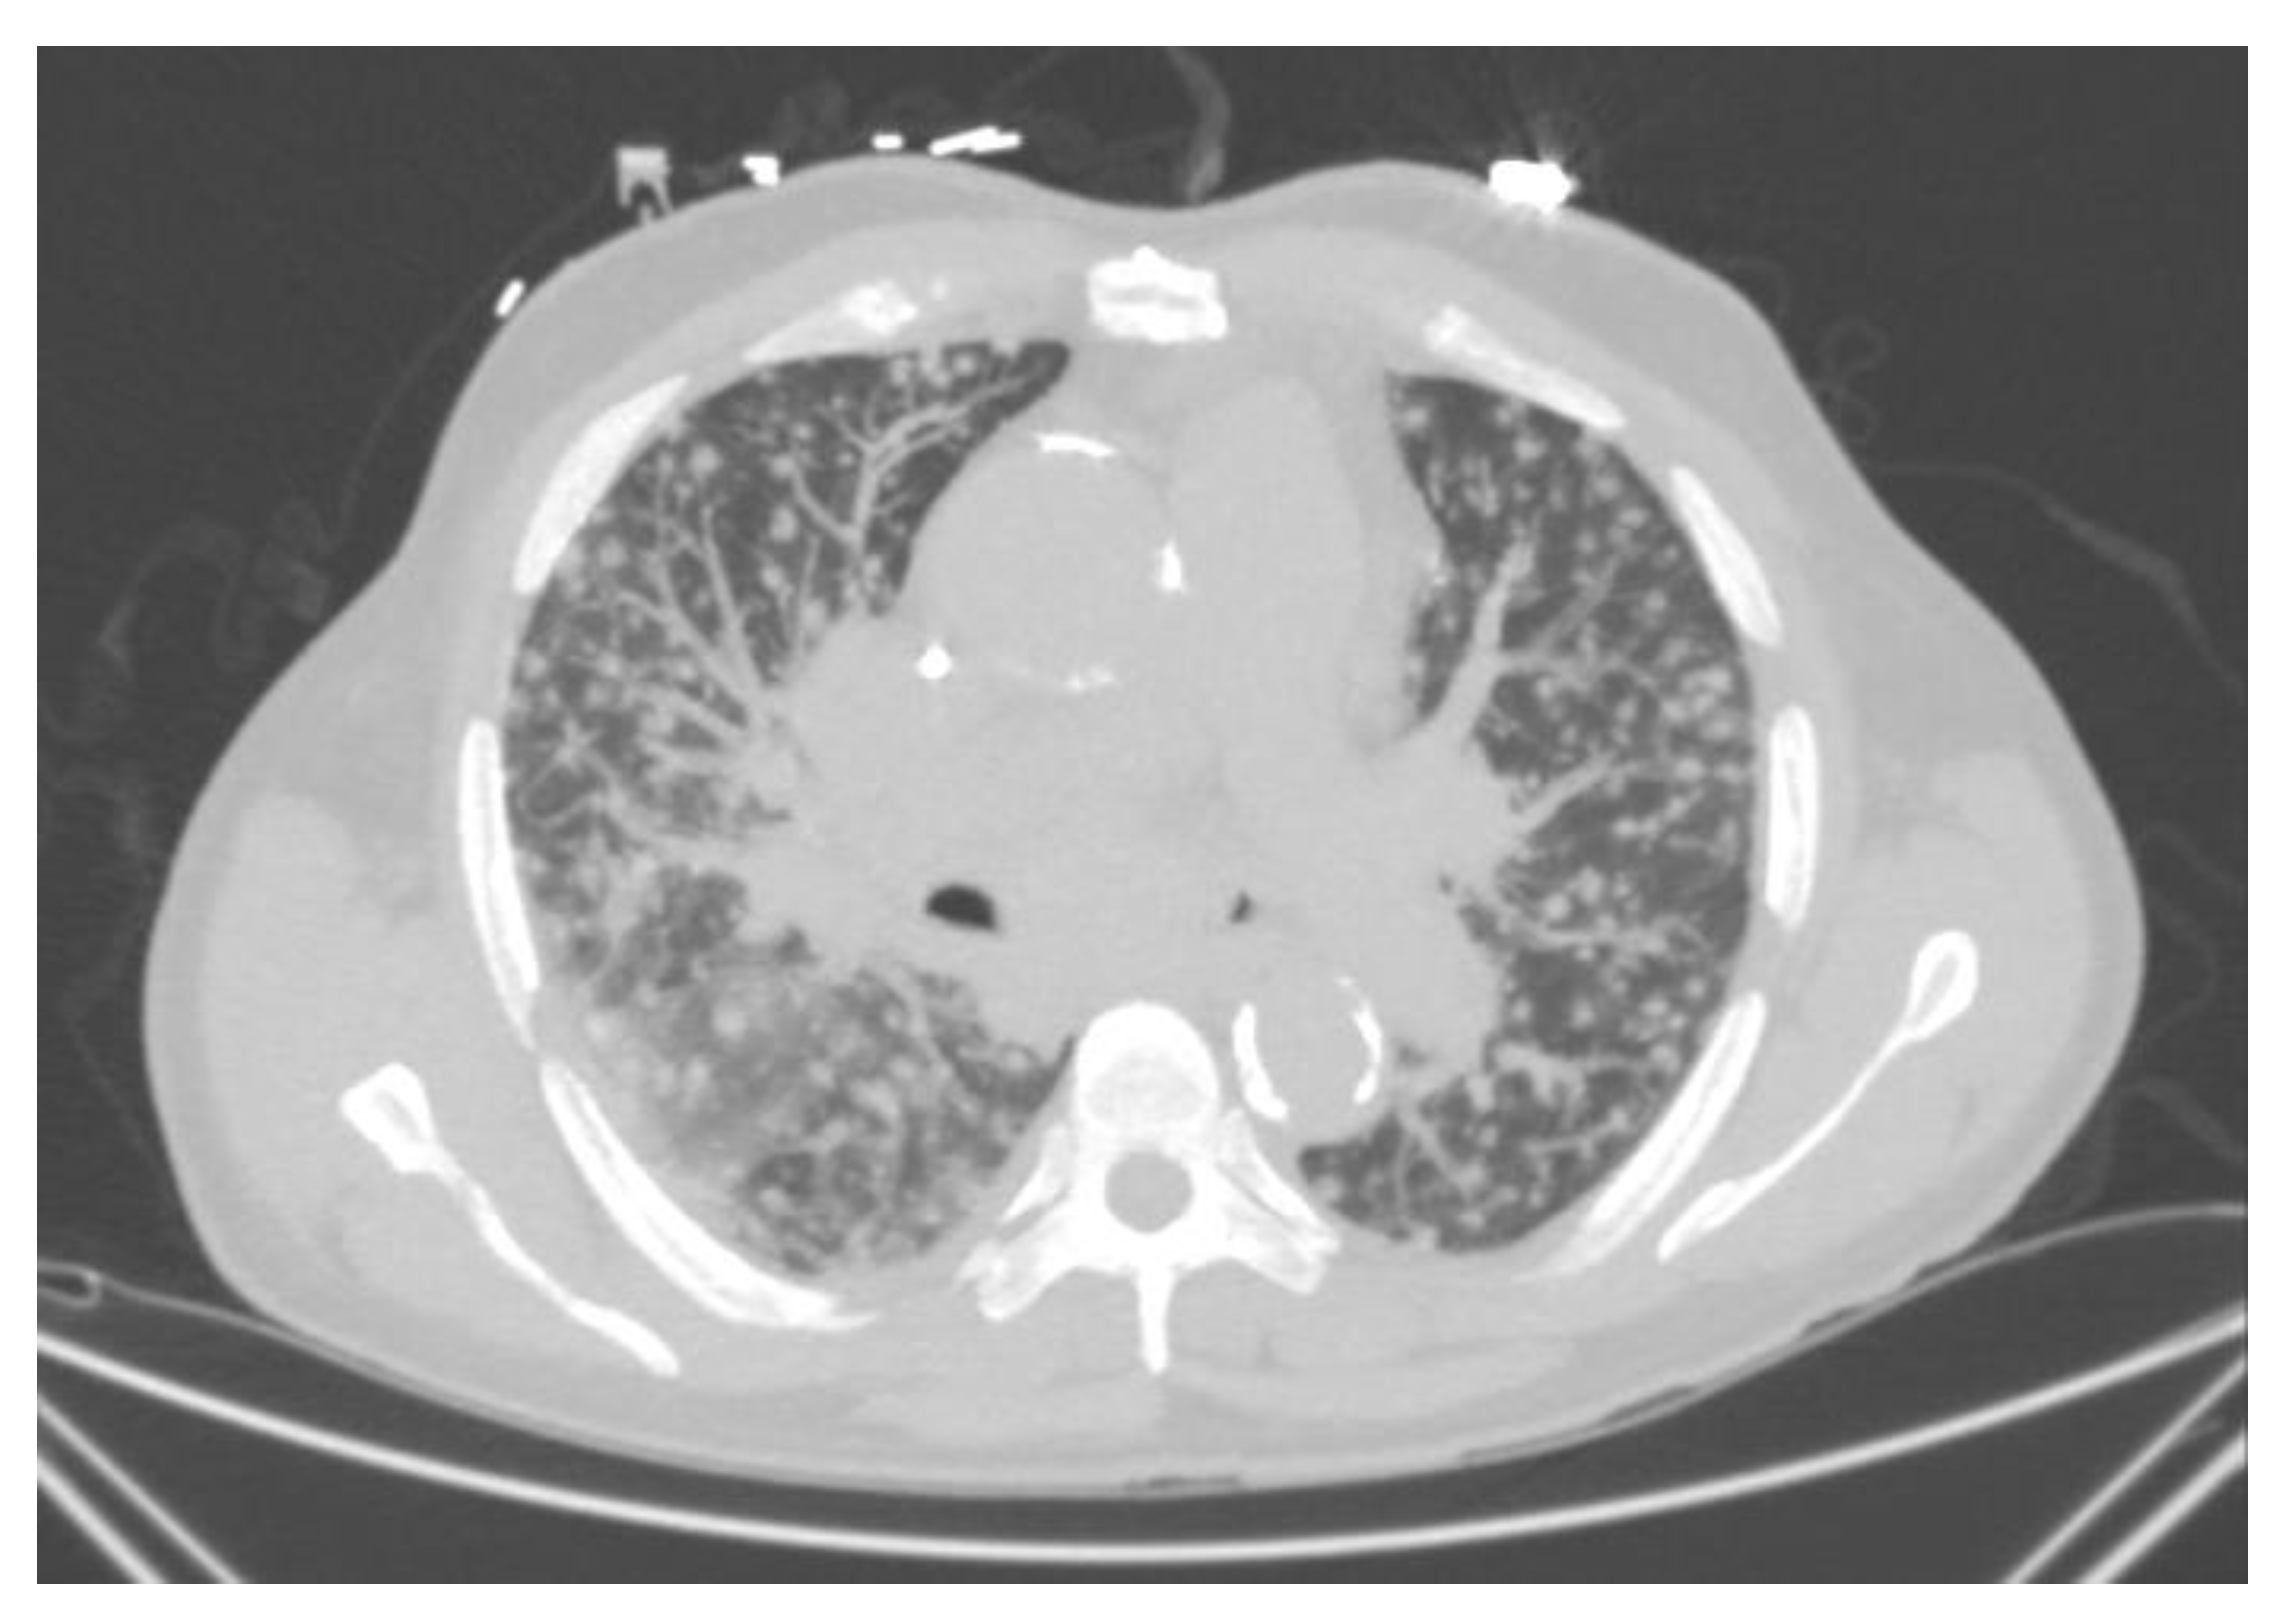

Symptoms resemble those of pulmonary tuberculosis, with patients experiencing low-grade symptoms including cough, weight loss, anorexia, increased sputum production, fever/chills, night sweats, and hemoptysis. In older cohorts, when patients presented with advanced disease, upper lobe cavitation occurs almost universally (98%) and most often on the right apex (84% vs. 52%). Modern reports show that cavitations may occur in a much smaller percentage of cases (30%) [68]. These cavities tend to have a thick wall and may have apical pleural thickening (Figure 6). Most of the patients will also have evidence of prior calcified pulmonary granulomas, though the presence of hilar or mediastinal lymphadenopathy is rare.

Figure 6.

Chronic cavitary pulmonary histoplasmois. Multiple thick wall cavitations in a patient with emphysematous disease.